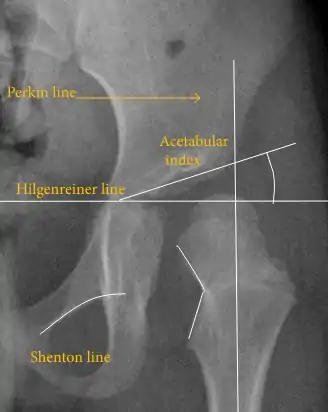

Hip dysplasia diagnosed by ultrasound[40] and projectional radiography ("X-ray").[41] Ultrasound imaging is generally preferred at up to 4 months due to limited ossification of the skeleton.[39][notes 1]

Despite the widespread of ultrasound, pelvis X-ray is still frequently used to diagnose or monitor hip dysplasia or for assessing other congenital conditions or bone tumors.[42] The most useful lines and angles that can be drawn in the pediatric pelvis assessing hip dysplasia are as follows:[42] Different measurements are used in adults.[42]